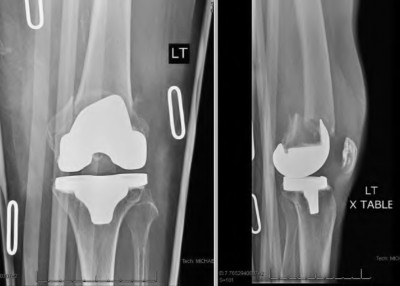

A 60-year-old male tennis player undergoes a unicompartmental knee arthroplasty (UKA) shown in Figures A and B. Which of the following statements regarding this procedure is true?

1) Compared to total knee arthroplasty (TKA), UKA more closely approximates native knee kinematics

2) Patients undergoing a UKA and TKA have equivalent blood loss and pain

medication requirements

3) Compared to their TKA counterparts, UKA patients have a slower return to function

4) There is no difference in range of motion at short or long term follow-up when compared with TKA

5) Postoperative hospital stay is equivalent for UKA and TKA patients

Figures A and B depict radiographs of a unicompartmental knee arthroplasty (UKA). UKA kinematics have been shown to most closely approximate native knee kinematics.

In an in vitro cadaver study, Patil et al found that TKA significantly changed knee kinematics while the unicompartmental replacement preserved normal knee kinematics.

Fisher et al performed a retrospective study comparing the short-term outcomes of small-incision unicompartmental knee arthroplasty (UKA) with standard total knee arthroplasty (TKA) in 91 consecutive patients older than 70 years. They found: 1) Blood loss was significantly more for the TKA group, as was the need for blood transfusion. 2) Patients with unicompartmental replacements had a much quicker return of function and discontinuation of pain medication. 3) While knee scores and ROM were similar preoperatively, both were better in the unicompartmental group at each postoperative time interval. 4) Narcotic use and length of hospital stay were also significantly less for the unicompartmental group. Therefore answers 2,3,4 and 5 are false.